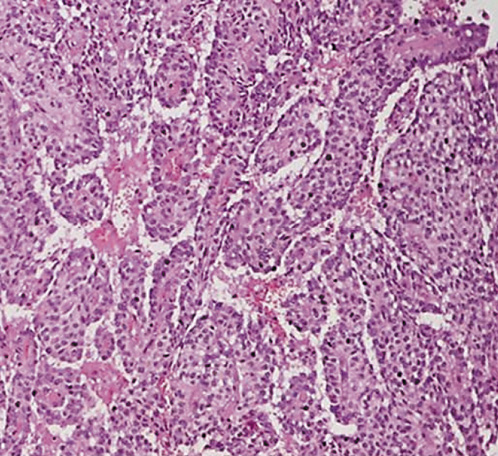

The patient successfully underwent pancreaticoduodenectomy. The histopathology of the surgical specimen revealed a tumor presenting a central ulceration, with hemorrhagic and necrotic areas mixed with solid areas extending to the duodenum and causing mucosal ulceration and fistulization to the duodenum (Fig. 4). None of the 7 lymph nodes evaluated were positive for malignancy. Microscopic analysis revealed sheets of uniform polygonal cells with pseudopapillary features (Fig. 5), with no margin involvement or perineural and angiolymphatic invasion. Immunohistochemistry was reactive for β-catenin, α1-antitrypsin, CD10, and Ki-67, which was consistent with an SPN of the pancreas.